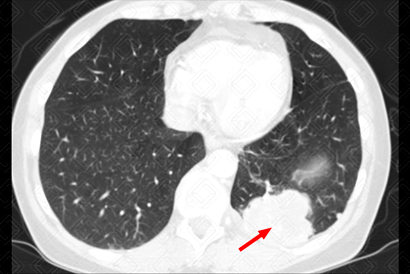

Texto alternativo para a imagem Figura 2. Créditos: Dra. Elazir Mota - Rio de Janeiro/RJ

Descrição das figuras 1, 2, 3 e 4: Tomografia computadorizada do tórax, seguida de reconstruções axiais e sagitais. Massa pulmonar, com contornos espiculados, localizada no segmento apical do lobo superior direito, medindo 3,2 cm x 1,5 cm x 2,2 cm (setas vermelhas).

Lembrando que, acima de 3 cm, a lesão já deve ser descrita como massa. Lesões menores que 3 cm são descritas como nódulos. Isso também é importante no estadiamento TNM (lesões ≥ 3 cm já são consideradas pelo estadiamento como T2).